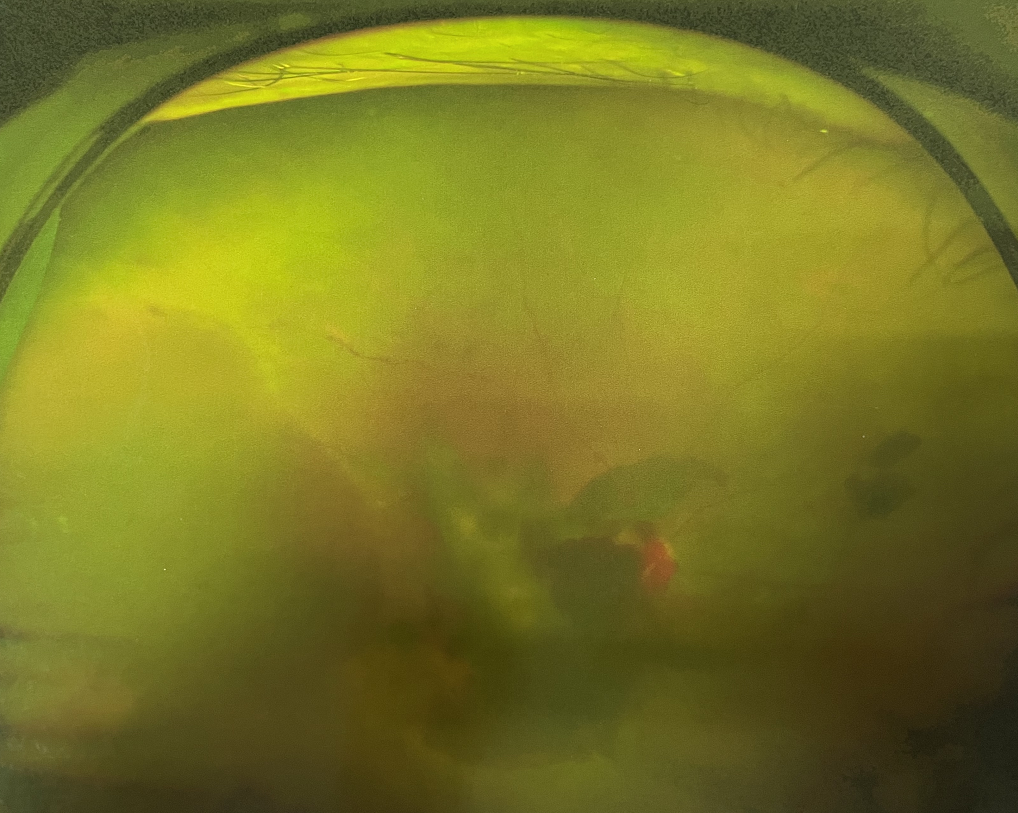

眼底出血多指玻璃體內(nèi),眼睛更深處的視網(wǎng)膜出血。通常情況下,肉眼難以發(fā)現(xiàn)眼底出血,而且發(fā)病初期眼睛也無(wú)明顯癥狀,只有借助專業(yè)的眼底檢查儀器才能觀察到異樣。那么眼底出血嚴(yán)重嗎?

誘發(fā)眼底出血的原因眾多,常見的有全身性血管病和血液病、視網(wǎng)膜血管異常、機(jī)械性阻塞、炎癥性疾病或免疫復(fù)合物侵犯血管壁等。

眼底出血嚴(yán)重嗎?其中,“三高”患者、高度近視患者和滲出性或濕性老年黃斑變性患者是眼底出血的高發(fā)人群。

醫(yī)生提醒,一旦眼睛出現(xiàn)視力下降、視物變形、視野缺損或眼前有黑影等視覺“異常”的情況,應(yīng)及時(shí)到醫(yī)院進(jìn)行眼底檢查,及早發(fā)現(xiàn),及早治療,以免貽誤病情。